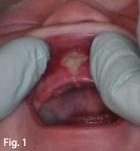

Post-op healing example of a baby's upper lip after frenectomy performed at Kids Smiles Pediatric Dentistry.

Lip Stretch:

• With clean hands, grasp the upper lip and lift up and back towards the nose. Hold this position for 5 seconds. (see fig 1)